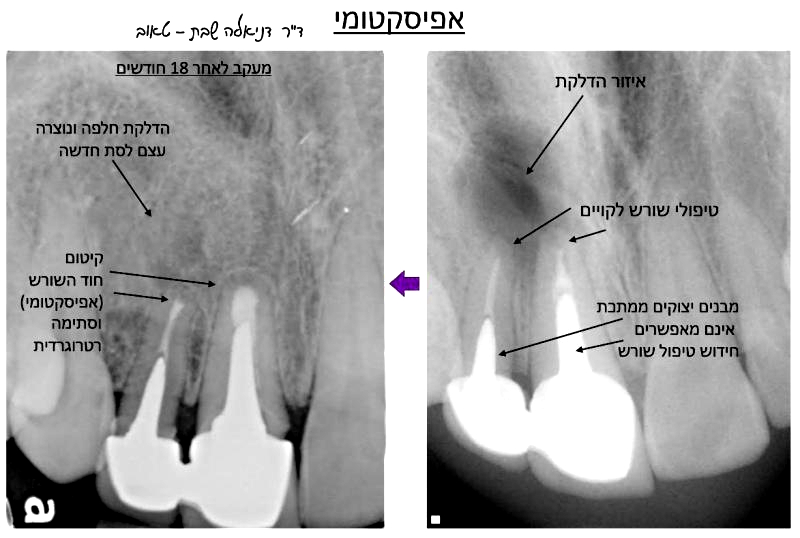

אם האבחנה היא שבוצע כבר טיפול שורש איכותי והבעייה היא אנטומית (למשל קצה השורש מעוקל בצורה כזו שלא ניתן להגיע אליו, או שקצה השורש מפוצל למספר תעלות קטנטנות שלא ניתן לטפל בהן, למשל), או שכבר בוצע חידוש טיפול שורש בצורה מיטבית והדלקת לא חלפה, או שכלל אין אפשרות לבצע חידוש טיפול שורש בגלל נוכחות של כתר ומבנה שאי אפשר להסידם, לעיתים הטיפול הוא אפיסקטומי – קיטום כירורגי של חוד השורש, במידה ויש סיכוי להצלת השן והישרדותה בפה.

בטיפול זה הרופא אינו מוריד את הכתר וניגש לטפל בצורה הרגילה, אלא מבצע פתח קטן בחניכיים, ודרכו חודר לעצם הלסת עד שמגיע לאזור הדלקת וקצה השורש הבעייתי. בעזרת מיכשור מיוחד קצה השורש נקטם (נחתך) ומוצא מתוך הלסת החוצה, והאזור עובר חיטוי יסודי והוצאת שרידי הדלקת או הציסטה שנוצרה שם. לעיתים גם יבוצע דרך הפתח הנ"ל בחניכיים ובעצם גם איטום מחדש של קצה השורש שנותר בכדי לשפר את הסיכוי לאיטום מלא ומיגור הדלקת (טיפול שנקרא "סתימה רטרוגרדית" או "טיפול שורש רטרוגרדי"). יש רופאי שיניים שגם מבצעים השתלת עצם אם הפגם הגרמי שנוצר הינו גדול, ויש רופאים שמותירים לעצם להחלים באופן ספונטני. הפתח בחניכיים ייסגר עם או בלי תפרים, תלוי בגודלו. אחוזי ההצלחה של טיפול זה כאשר מאובחן נכון ומבוצע היטב הינם 85-90% הצלחה.

לאחר הביקורת הראשונית במרפאה והוצאת תפרים אם בוצעו, יש צורך במעקב ממושך אחרי האזור שטופל, קלינית ורנטגנית. אם הטיפול הצליח, מושג ריפוי במהלך הזמן ואפשר לראות בצילומי הרנטגן שהחלל מתמלא בעצם לסת חדשה ואיכותית. בדרך כלל המעקב הוא מדי מספר חודשים ואף שנים. אם לא יושג ריפוי גם לאחר אפיסקטומי, או שהמצב יחמיר, ייתכן ויהיה צורך בעקירת השן.